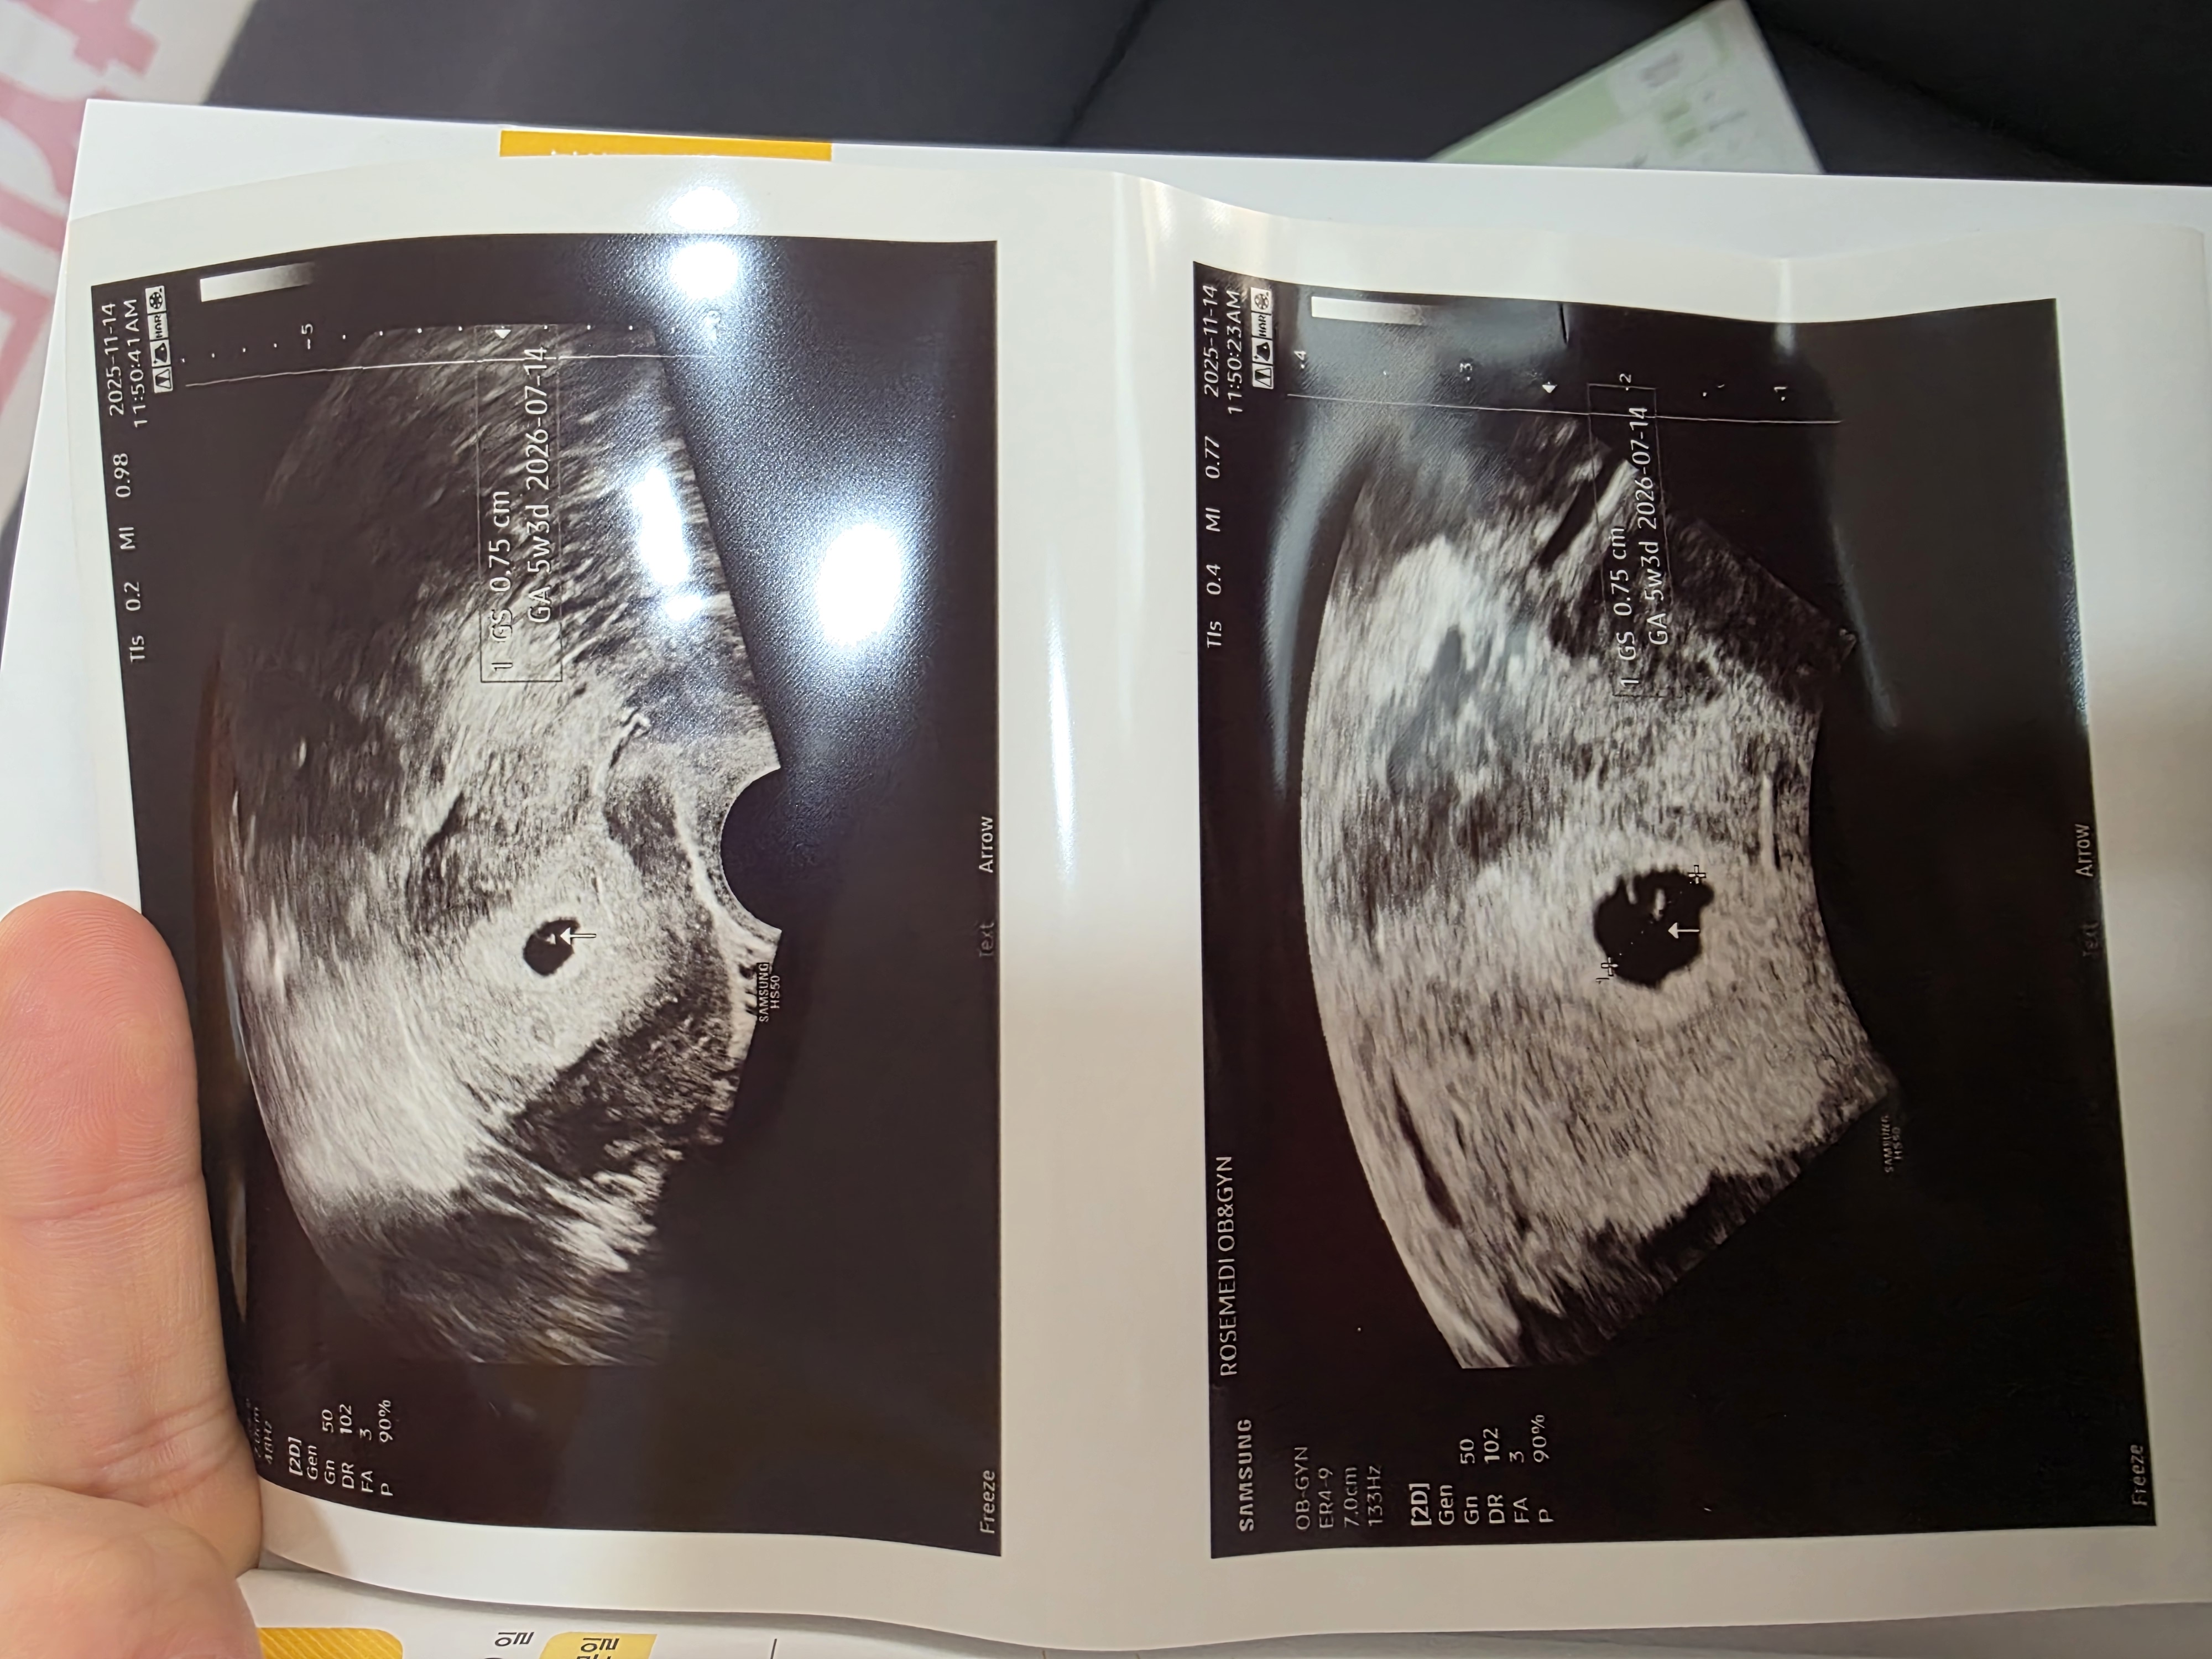

오늘 난황 보고왔어요!

오늘 난황보고왔어욯 아기집 크기는 0.75cm라는데 보통 크기겠죠?ㅎ 왤케 작게 느껴지는지 일주일만에 쑥쑥 크고있네요 저번주는 0.27cm였어요ㅎ 일주일 뒤에는 심장 뛰는 소리듣는다는데 일주일 왤케 길어요ㅠ